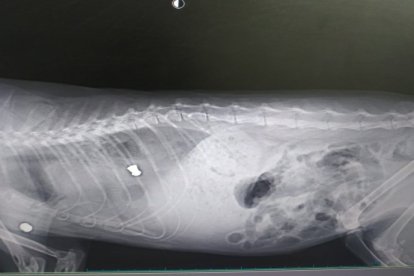

Radiografía donde se ven los perdigones.